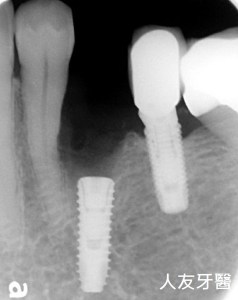

患者林伯伯年齡大約70歲,因左下第二小臼齒咬裂斷掉,經由醫生判斷建議拔除之後植牙搭配數位支柱(Abutment),加全鋯牙冠,已利恢復正常咬合。

當什麼時候醫師會選擇數位支柱(Abutment)呢?

牙齒長度較長時,或因種植的角度限制而找不到合適的支柱,此時醫師就會選擇使用數位支柱(Abutment)來使用。